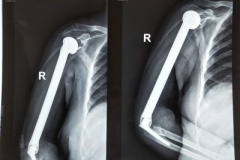

健康科普:患骨腫瘤一定要截肢嗎?

健康科普:患骨腫瘤一定要截肢嗎? “患骨腫瘤就要截肢”的說法是一個誤區(qū),截肢僅是治療末期、惡性度高或者發(fā)展很快的惡性腫瘤的方法之一。

健康科普:如何判斷骨腫瘤?

健康科普:如何判斷骨腫瘤?  一般而言,體表的軟組織腫瘤比較好發(fā)現(xiàn),但是被豐富的肌肉組織等包圍的骨骼病變在早期則不容易被發(fā)現(xiàn),所以專家提倡早發(fā)現(xiàn)、早治療。